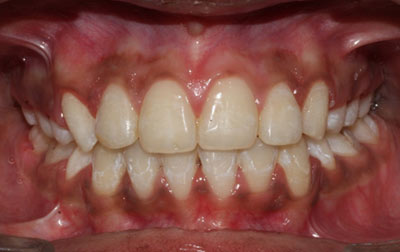

Smile makeover:

Radiating confidence through a beaming smile can truly uplift your spirits. A captivating smile holds significant sway in social and professional spheres, enhancing your overall appeal. However, numerous individuals refrain from revealing their teeth in public or photographs due to personal dissatisfaction. If you find yourself in this category, why not consider allowing us to assist you in attaining the smile you've always envisioned? Embark on a journey toward your ideal smile with our transformative smile makeover. A smile makeover transcends the mere resolution of dental issues as they arise. It constitutes a holistic plan to rejuvenate your smile, intricately tailored to complement your distinct facial features and aesthetic inclinations. The outcomes are nothing short of remarkable—both in terms of your visual transformation and the surge of newfound confidence you'll experience.

Invisalign: Invisalign is a revolutionary orthodontic approach using transparent, removable aligners. Virtually invisible, it provides discreet teeth straightening, ideal for those concerned about appearance. The aligners are easily removable, enabling hassle-free oral care and allowing consumption of any food. They offer greater comfort as they lack wires and brackets, with gradual adjustments for a comfortable experience.

Metal braces: Metal braces are the traditional orthodontic choice, using metal brackets and wires to achieve comprehensive teeth straightening. They excel in correcting complex alignment problems and are a reliable option. Metal braces are known for their durability and effectiveness, often resulting in shorter treatment times. Regular adjustments allow for precise control over tooth movement, making them a time-tested solution for achieving optimal alignment.